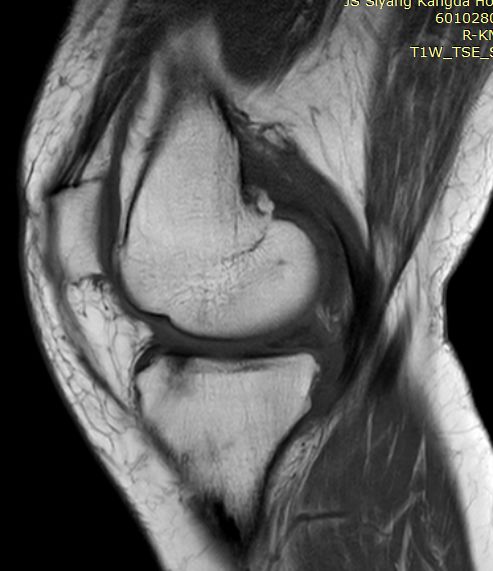

有时前交叉韧带损伤或撕裂,须与半月板撕裂相鉴别,如下例

箭头是撕裂的内侧半月板,前交叉韧带冠状面是连续的,下端胫骨附着处小片绪状高信号影,提示损伤或部分撕裂。